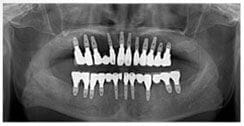

X 光片

術前X光片

術後X光片